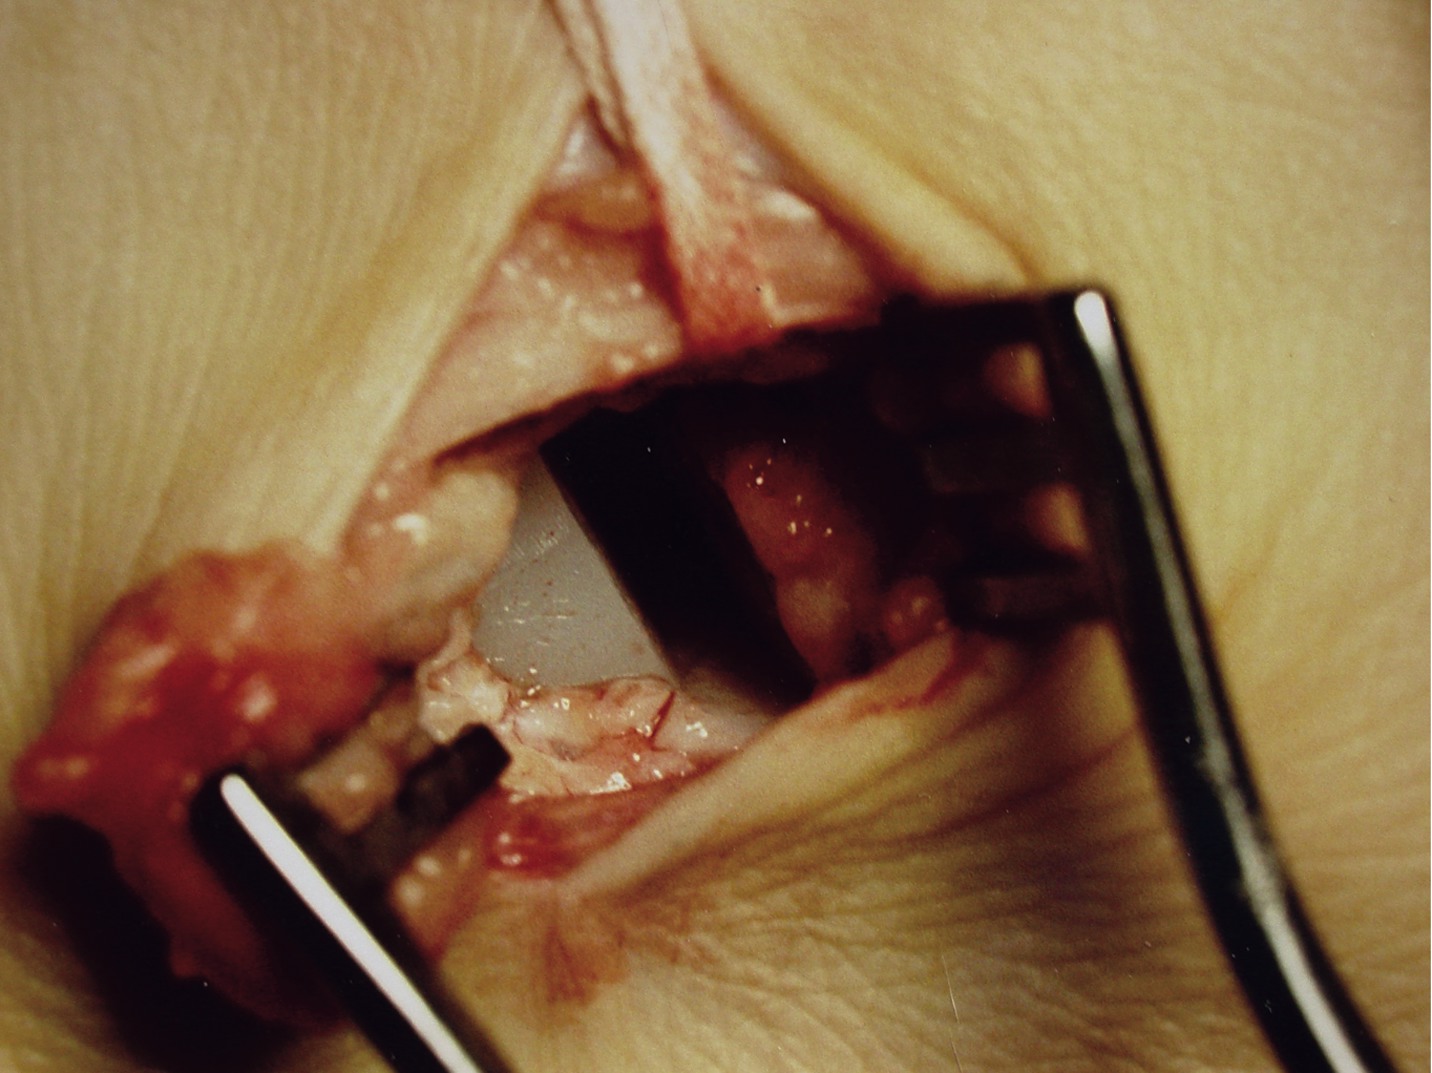

Bioabsorbable implants have gained popularity for a number of reasons. Perhaps the leading reason is the fact that they do not require a second procedure for removal. Metallic fixation can be problematic due to corrosion, biomechanical stiffness and, most importantly, stress shielding.13 Since the absorbable implants exhibit rigidity closer to that of bone, there is a significant decrease in stress shielding.5 The initial stability is adequate for healing but the implant gradually degrades and the stresses are transferred to the surrounding tissues.13 Another benefit of bioabsorbables is their radiolucency. They will not produce the X-ray scatter on magnetic resonance images or computed tomographic scans associated with metal fixation.15 The most cited complications associated with bioabsorbable implants are sterile sinus tracts, osteolysis at the site of insertion and late foreign body reactions. Other negative attributes include a finite life span, a diminishing strength profile over time and increased cost.9 Out of the aforementioned problems, adverse tissue reactions are of most concern to the surgeon. Böstman and Pihlajamäki reported that 4.3 percent of 2,528 patients experienced a clinically significant local inflammatory, sterile tissue reaction.16 Upon further analysis, the rate of reaction to PGA implants in the study was 5.3 percent versus 0.2 percent for PLA implants. Also, PGA reactions appeared at an average of 79 days versus 4.3 years for the lone PLA reaction. The reaction presents as a painful, erythematous, fluctuant papule at the site of the implant. Histopathologically, there is a nonspecific, inflammatory foreign body reaction with numerous mononuclear phagocytes and multinucleated foreign body giant cells.16 Radiographically, about one half of patients with an adverse tissue reaction will exhibit osteolysis at the site of implantation.17

To answer the question of whether bioresorbable implants work, the answer appears to be yes. Although there are only two published studies on bioresorbable implants in juveniles, both of which are favorable, the design characteristics of the bioBlock implant are nearly identical to those of the well documented MBA implant. Accordingly, one would expect similar results. As to the question of whether the bioBlock implant is better, the answer is unclear at this time. The company states that one potential advantage is for parents who do not want a permanent metallic implant in their child’s foot. Although this is true, this concern is only raised in a small number of patients. As noted earlier, subtalar joint pain is the most common complication of arthroereisis devices. If we assume the implant was the correct size and was properly inserted, will resorbable implants lower this complication rate? Sinus tarsi pain is, in part, a reactive inflammatory response secondary to the compressive forces between the talus, calcaneus and the interposed implant device. As the implant begins to resorb and lose its structural integrity, these forces should diminish with subsequent reduction of clinical symptoms. Needleman noted that, in most patients, the sinus tarsi pain began shortly after weightbearing and ultimately required removal in 9 of 12 feet between seven and 12 months postoperatively.6 Therefore, if the implant does not lose its structural integrity until 18 months postoperatively in children as reported by Giannini, the implant will probably not resorb quickly enough to prevent its removal secondary to sinus tarsi pain.24 Resorption times for bioabsorbable subtalar joint implants are unknown in adults but probably exceed that of children due to decreased vascularity. Kinetikos Medical recommends maximum patient body weights for each diameter implant. For an 8 mm implant, the maximum body weight would be 150 lbs. For a 9 mm implant, it would be 180 lbs. For a 10 mm implant, it would be 220 lbs. For an 11 mm implant, it would be 250 lbs. For a 12 mm implant, it would be 250 lbs. Exceeding these limits may cause the implant to deform. It is unlikely this alteration of shape will result in loss of correction but it may reduce compressive forces within the sinus tarsi. Additionally, the implant, due to its viscoelastic properties, does have the capacity to deform under pressure. These factors may lessen the incidence of sinus tarsi pain. Loosening is rarely a problem with most sinus tarsi implants that are properly inserted. Soft tissue ingrowth helps to stabilize these implants, which are not inserted into bone. Scar tissue encompasses the implant and occupies the spaces between the threads and central cannula. With resorbable implants, as the structure loses its integrity, this stability will be lost and implant loosening may occur. If removal of the implant or its fragments is required, this could prove difficult as the material is radiolucent. Although the incidence of adverse reactions to PLLA is less than 1 percent, foreign body reactions are still possible, especially when the implant fragments and shards are dispersed into the soft tissues. The final and perhaps most important question to consider is the long-term efficacy of resorbable sinus tarsi implants for the correction of flatfoot deformity. Needleman demonstrated no significant change in radiographic parameters after implant removal at an average follow-up time of nearly four years.6 All patients had either a heel cord lengthening and most had adjunctive forefoot procedures so it is difficult to isolate the effect of implant removal. However, these findings are consistent with other reports in the literature (among both adults and children) of persistent correction despite implant removal or resorption. An “arthrofibrosis” of the subtalar joint appears to develop and this may ultimately limit motion in the implant’s absence.